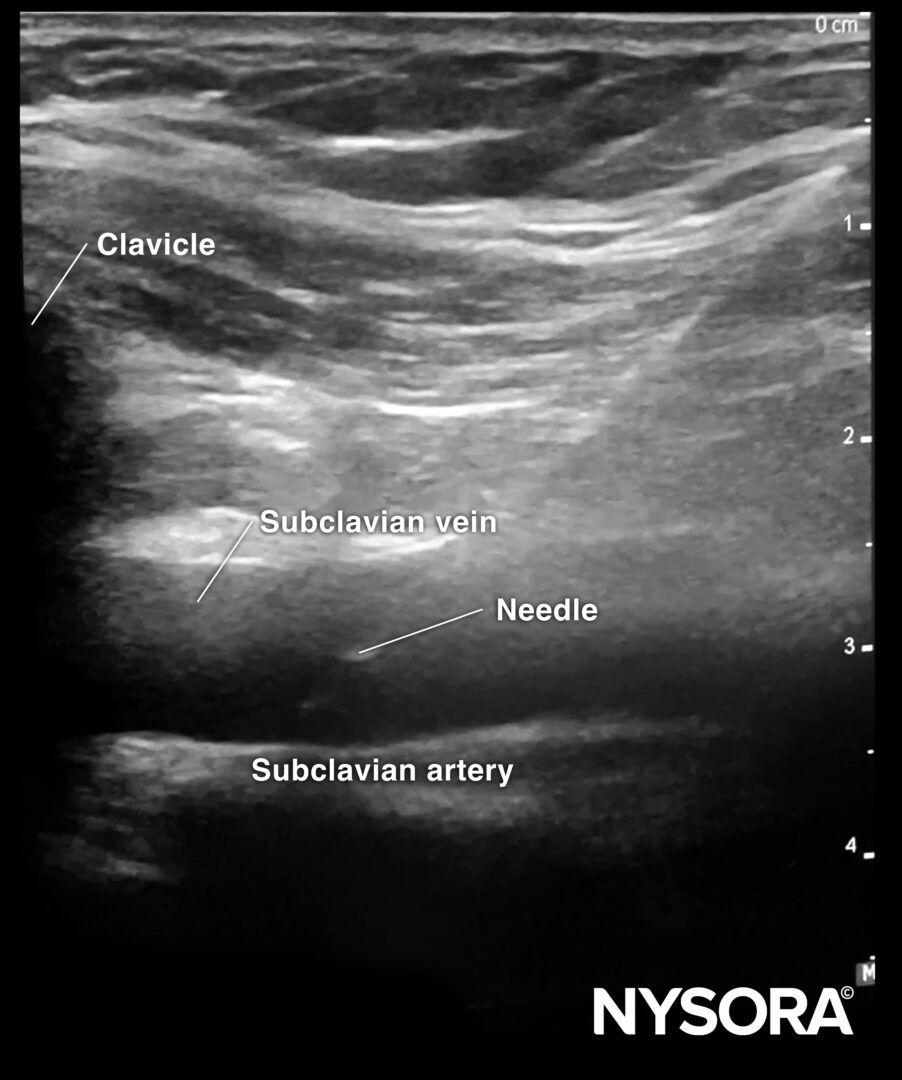

First, the transducer is placed in a longitudinal orientation to the clavicle next to the deltopectoral groove. Identify the subclavian artery and vein, and position the vein in the middle of the screen. Rotate the transducer until the vein is seen in line. Now, you should also see the bony shadow of the clavicle.

Sonoanatomy for subclavian vein cannulation.

The needle is inserted in-plane in a cranial direction.

In-plane needle insertion in the subclavian vein.

- An in-plane or oblique technique allows the needle to be visualized during the full needle path. This decreases the chance of unintentional pleural puncture during subclavian vein cannulation.